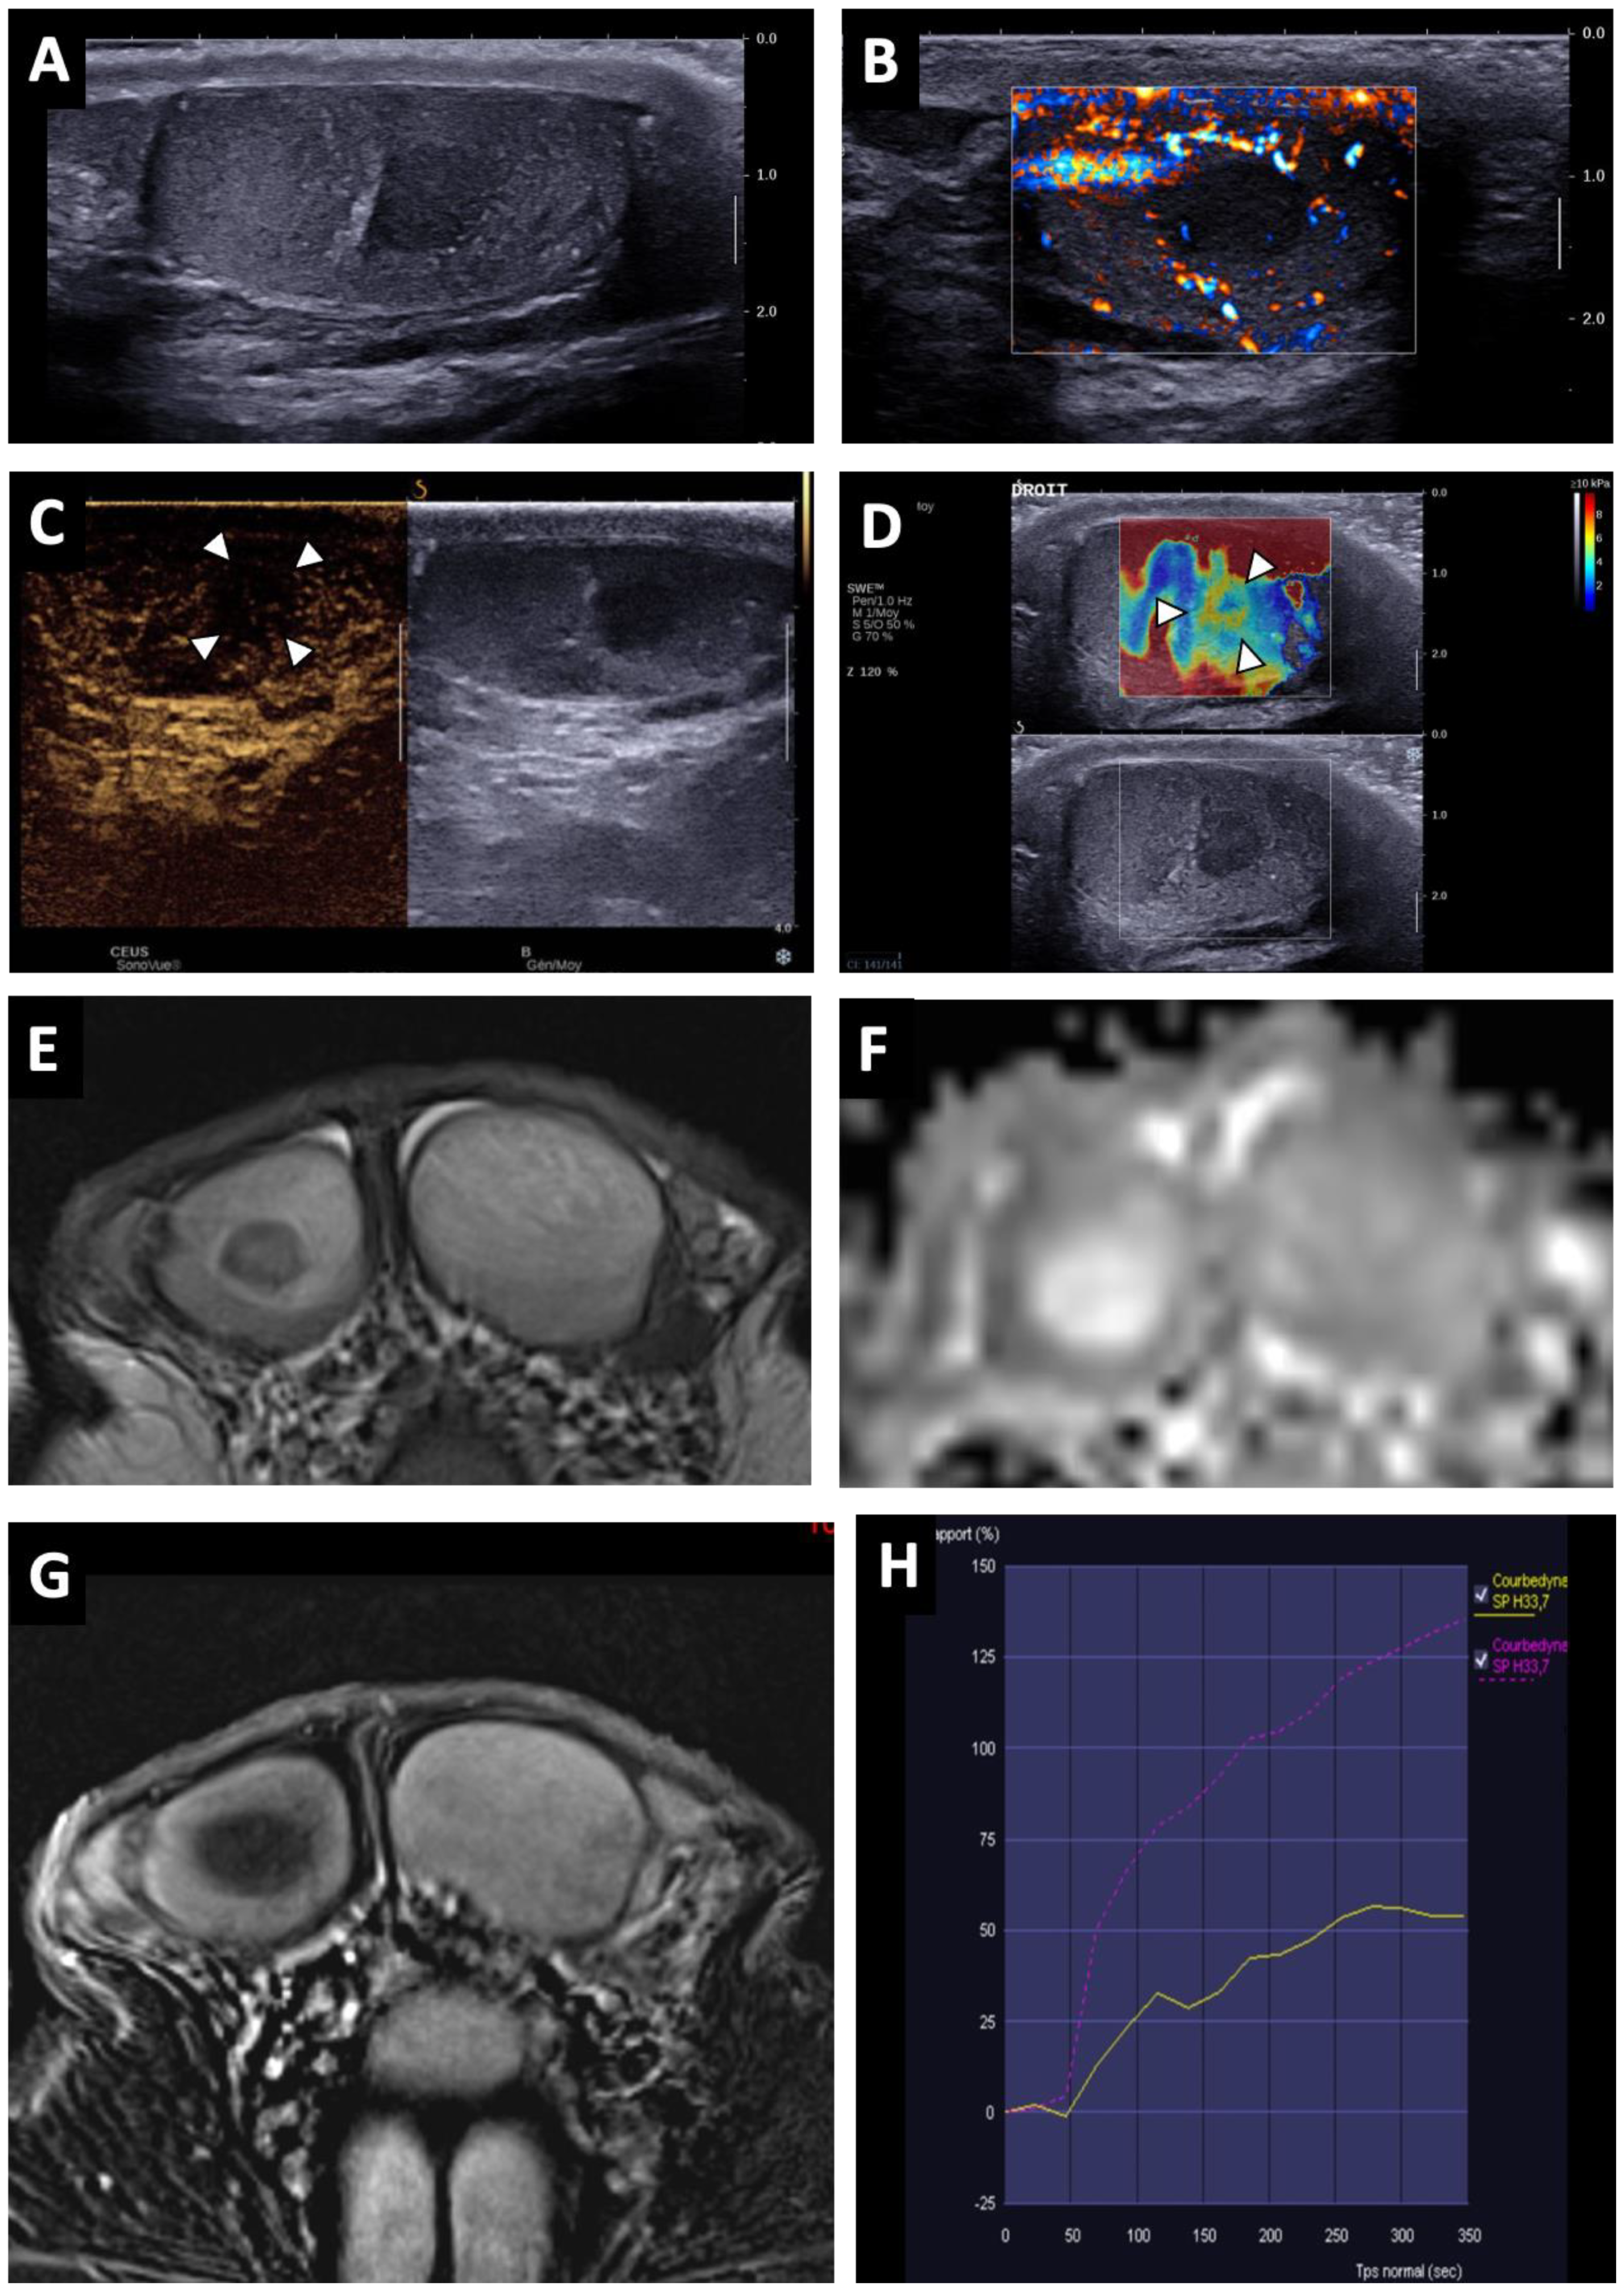

Figure 2. BOTT of the right testis in a 40-year-old man (symptomatic retroperitoneal nodes). Longitudinal image of US on Colour Doppler mode showing poorly circumscribed hypoechoic and hypovascularised nodular areas (white arrowheads) (A). Shear-wave elastography mapping showed a focal induration (B) (different slice plane from image (A)). Axial T2W image showed multiple irregular areas with a hypo-intense signal (white arrows) (C). Axial T1W image without a detectable focal lesion (D). ADC map of the diffusion sequence demonstrated a focal area with an elevated ADC value compared with the contralateral testis (black arrowheads) (E). After the intravenous injection of gadolinium chelate, confluent areas with reduced enhancement were visible (note that these areas are overlapping the nodules visualized in T2) (F).

Lesions appeared as hypoechoic nodular areas (Figure 2 and Figure 3) for 44 patients (91.7%) and an entire hypoechoic testis infiltration for 4 (8.3%). The lesion was singular in 36 patients (75%), there were 2 nodules in 3 patients (6.3%) and more than 2 in 9 patients (18.8%). Conventional US findings results are summarized in Table 2.

All lesions had ill-delineated margins. In 42 cases (87.5%), the lesions appeared hypovascular compared to normal parenchyma (Figure 2 and Figure 3). In six patients, a hypervascular nodule with sharp boundaries was found within (four cases) or peripheral to (two cases) a hypovascular nodular area using CDUS, and corresponded to residual seminomas upon pathological analysis. One patient, who was finally diagnosed with a partially regressed seminoma, had no focal US abnormality that was suggestive of a viable tumour.

SWE exhibited a focal area of increased stiffness (Figure 2B and Figure 3D) corresponding to hypoechoic lesions in 37 of 40 patients (92.5%). In three patients (7.5%) there was no detectable focal stiffness abnormality. Stiffness measurements in 30 patients indicated a mean value of 13.7 ± 8.4 kPa in areas of elevated stiffness versus 2.6 ± 1.3 kPa in normal testicular parenchyma (significant difference, p < 0.01). The mean stiffness ratio was 5.3 ± 2.4. No significant difference was found when comparing hypervascular nodules and the hypovascular surrounding areas in the case of partial tumour regression.

BOTTs appeared as round or oval nodules (81%) (Figure 3 and Figure 4) or a focal area with irregular boundaries (19%) on the T2 sequences (hyposignal). No lesions were visible on the T1 sequences (isosignal) (Figure 4C).

The diffusion-weighted sequences showed nodular areas of reduced signal with increased ADC values (mean value: 2 ± 0.3 × 10−3 mm2/s) (Figure 2E and Figure 3F) compared to contralateral parenchyma (mean value: 1.3 ± 0.3 × 10−3 mm2/s) in all patients (significant difference, p < 0.01). The mean ADC ratio was 1.6 ± 0.3. Within these areas with increased ADC values, a restrictive nodule (Figure 4B) was detected in six of the seven patients that were diagnosed with a partially regressed testicular tumour.

Dynamic contrast-enhanced sequences showed areas of reduced enhancement in all cases. The size of this area matched that of the lesion on the T2 sequences (Figure 3G) in 11 patients (26.2%), and in 31 patients (73.8%) it overlapped the lesion with reduced enhancement extending to the peripheral parenchyma (Figure 2F and Figure 4D). In the cases of partial tumour regression, dynamic contrast-enhanced sequences revealed early and strongly enhanced focal abnormalities within areas of reduced enhancement, corresponding to nodules in six patients (Figure 4D), and an ill-delineated area with increased enhancement in one (corresponding to the patient in whom no focal abnormality that was suggestive of a viable tumour was found upon US examination).

Time–signal-intensity curves were created (Figure 3H) for 23 patients with complete tumour regression, showing type 0 curves in 7 cases and type 1 in 16 cases. Type 2 (two patients) or 3 (five patients) time–signal-intensity curves were observed in focal lesions corresponding to viable seminoma.